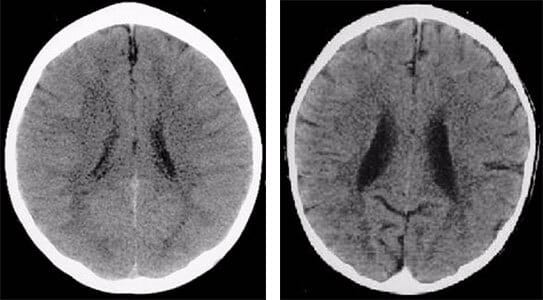

Chronic stress in childhood affects the developing brain, leading to alterations in brain structure and function, particularly in areas associated with emotional processing, stress regulation, and social cognition. Brain scans of children who have experienced severe or continued neglect show smaller brain size and abnormal cortical development.